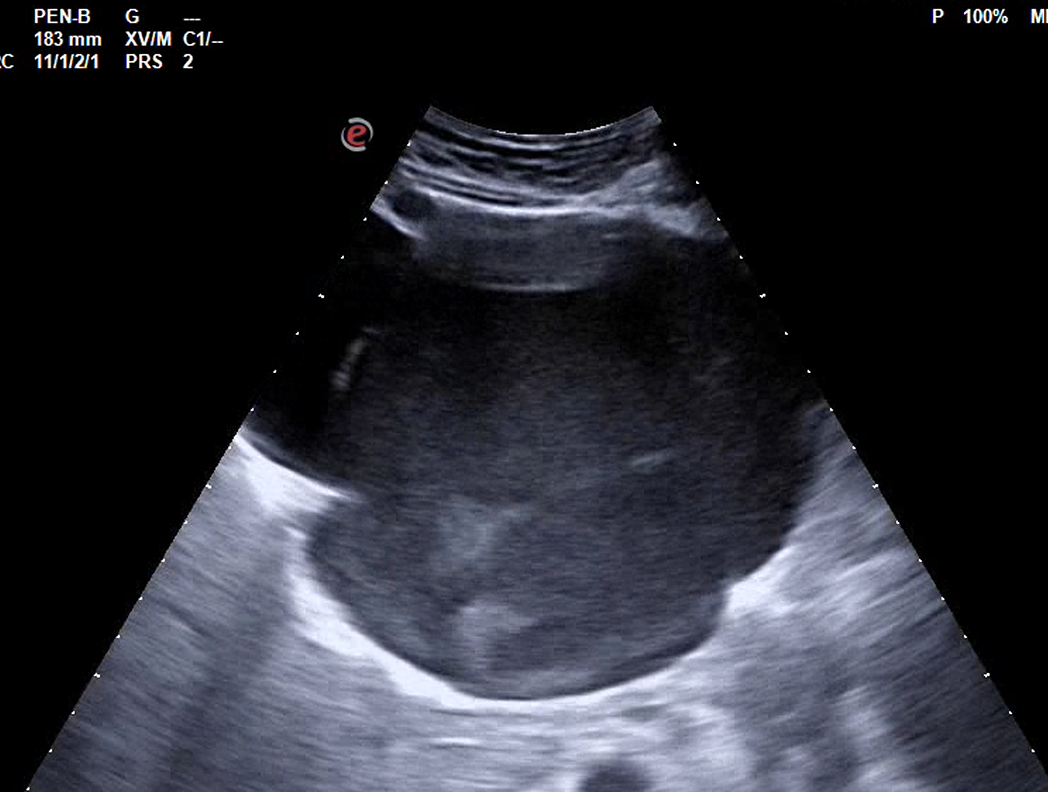

Realizamos ecografía abdominal en centro de salud, objetivándose grandes masas abdominales, no vascularizadas, de contenido hipoecogénico y heterogéneo, en todo el abdomen, sin distinguir si dependencia hepática o pancreática con leve dilatación de vía biliar intrahepática, vía extrahepática normal.